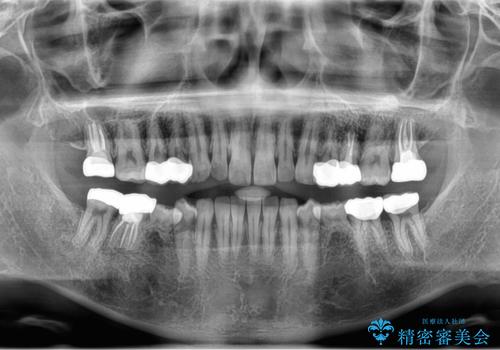

- 口の中を予算の範囲内でできるだけきれいにしたいとのことで来院された患者様です。

矯正治療と虫歯治療を組み合わせてご提案しましたが、ご予算との兼ね合いで虫歯治療のみを行うこととなりました。

奥歯は十分な歯の高さがなかったため、クラウンをかぶせる前に歯周外科治療で歯の高さを出しています。

歯科に通うようになってから磨き残しの状態も改善されていきました。